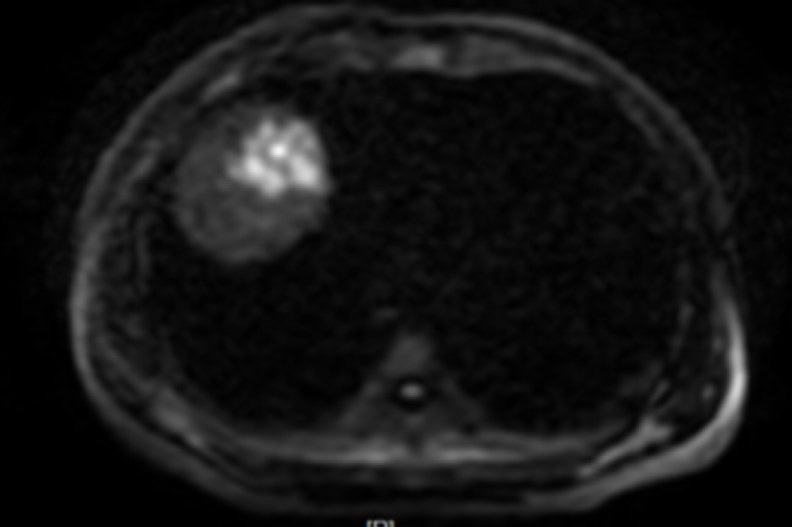

MRI显示疗效达到完全缓解(CR)